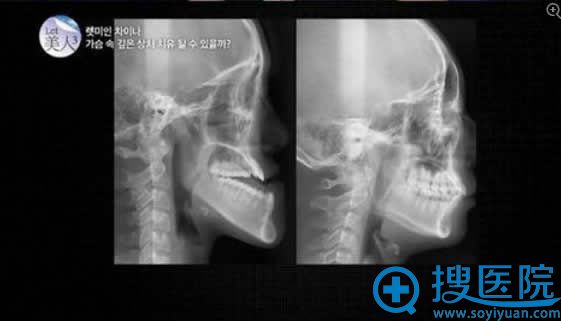

let美人郭芳媛术前下颌X光片

她虽然只有18岁,但自从3岁时从椅子上跌落后,上颚几乎不再生长,下颚却越长越长,成了如今“地包天”的样子。除相貌外,因牙齿咬合不齐,她咀嚼食物也很吃力。